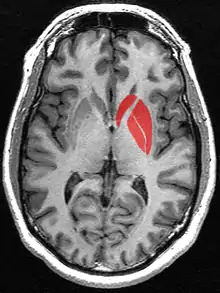

Striatum

The striatum, or corpus striatum[5] (also called the striate nucleus), is a nucleus (a cluster of neurons) in the subcortical basal ganglia of the forebrain. The striatum is a critical component of the motor and reward systems; receives glutamatergic and dopaminergic inputs from different sources; and serves as the primary input to the rest of the basal ganglia.

Functionally, the striatum coordinates multiple aspects of cognition, including both motor and action planning, decision-making, motivation, reinforcement, and reward perception.[2][3][4] The striatum is made up of the caudate nucleus and the lentiform nucleus.[6][7] The lentiform nucleus is made up of the larger putamen, and the smaller globus pallidus.[8] Strictly speaking the globus pallidus is part of the striatum. It is common practice, however, to implicitly exclude the globus pallidus when referring to striatal structures.

In primates, the striatum is divided into a ventral striatum, and a dorsal striatum, subdivisions that are based upon function and connections. The ventral striatum consists of the nucleus accumbens and the olfactory tubercle. The dorsal striatum consists of the caudate nucleus and the putamen. A white matter, nerve tract (the internal capsule) in the dorsal striatum separates the caudate nucleus and the putamen.[4] Anatomically, the term striatum describes its striped (striated) appearance of grey-and-white matter.[9]

The striatum is the largest structure of the basal ganglia. The striatum is divided into a ventral and a dorsal subdivision, based upon function and connections.